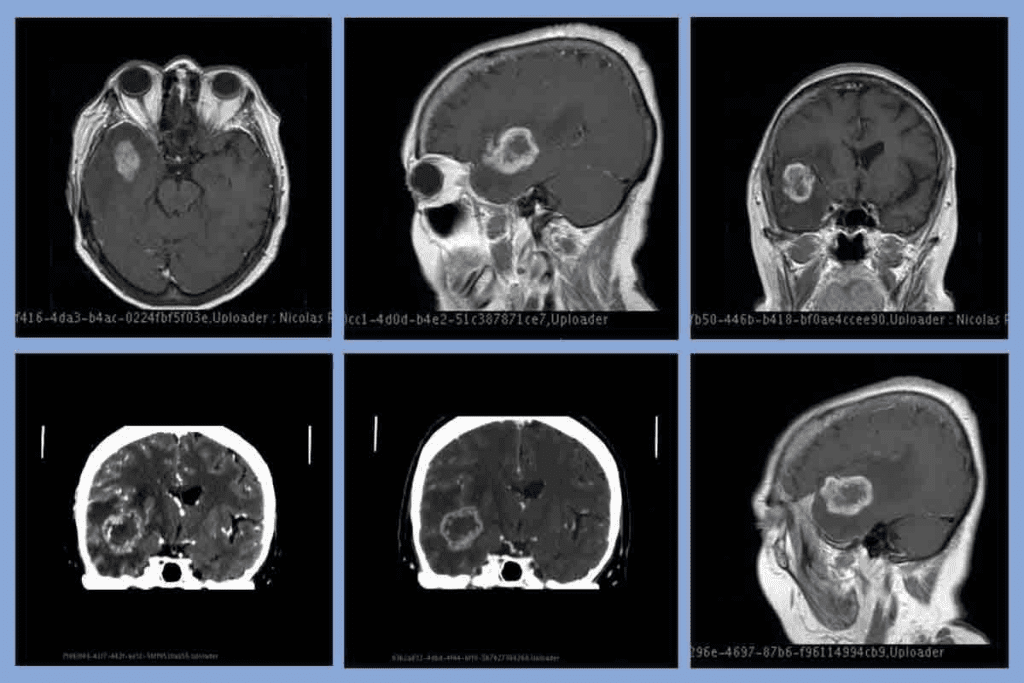

Gliomas and Glioblastomas: Most Common Malignant Brain Tumors in Adults

Gliomas and glioblastomas are the most common brain tumors in adults. They start from the brain’s glial cells, which protect neurons. Knowing about gliomas and glioblastoma helps in finding better treatments.

Glioblastoma: Aggressive Growth and Characteristics

Glioblastoma, or glioblastoma multiforme (GBM), is the most aggressive glioma. It makes up about 14-16% of brain tumors and up to 78% of malignant ones. It grows fast and spreads into the brain, making surgery hard.

Diagnosing glioblastoma usually means a short survival time, about 15 months. But survival can vary based on age, health, and how much of the tumor is removed.

Treatment Challenges and Survival Rates

Treating glioblastoma is tough because of its aggressive nature and the blood-brain barrier. Current treatments include surgery, radiation, and chemotherapy with temozolomide.